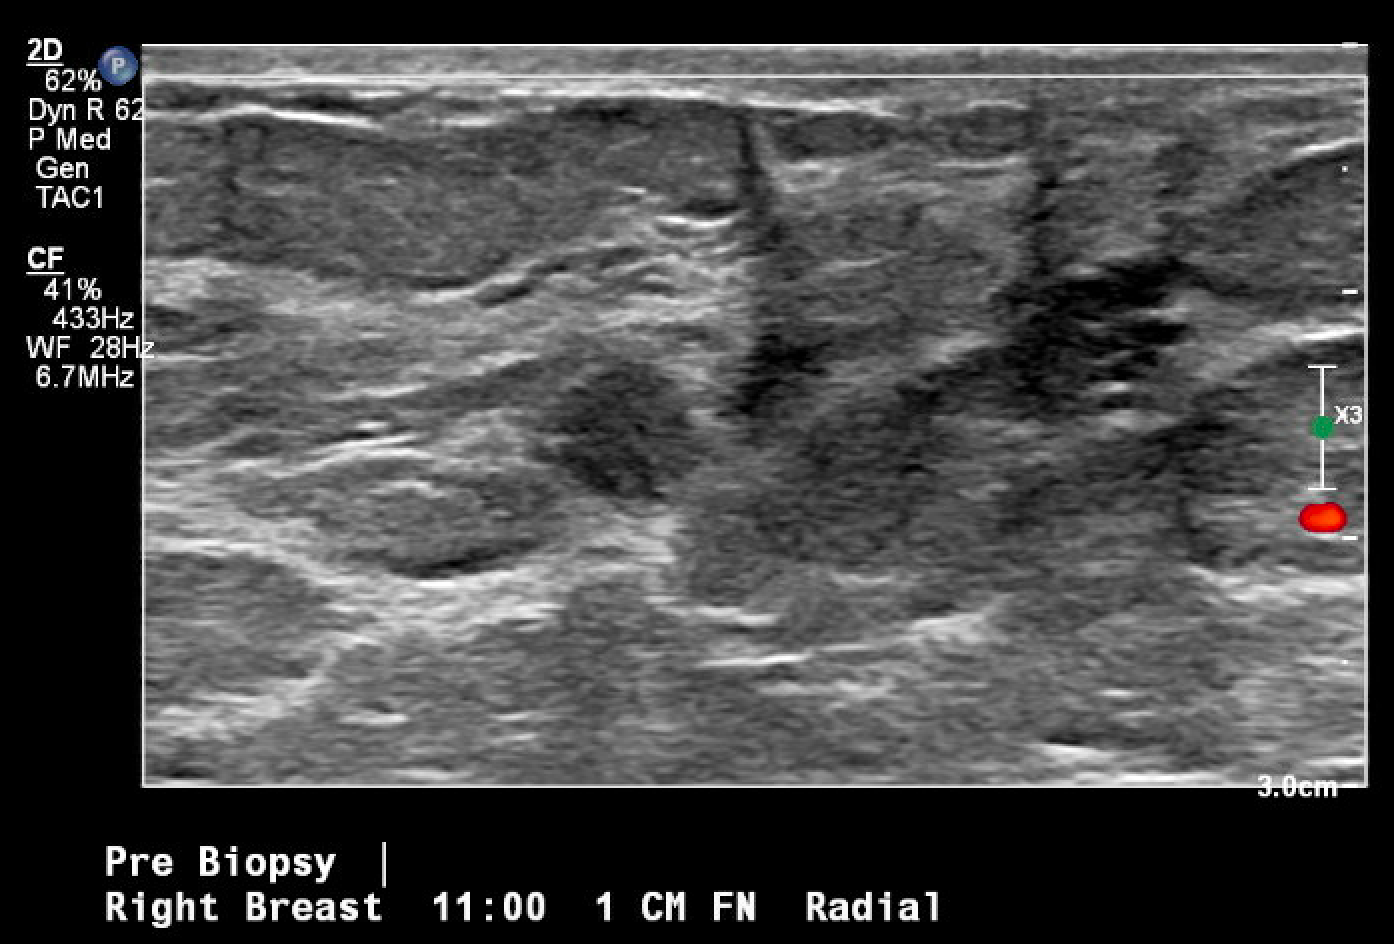

Se trata de una mujer premenopáusica de 46 años, sin antecedentes médicos o quirúrgicos, que acudió inicialmente a la clínica de cirugía mamaria después de que su mamografía anual de cribado descubriera una masa mamaria derecha no palpable de 0,6 x 0,8 x 0,7 cm a las 11 horas (oc), a 1 cm del pezón (FTN) (Figura 1). Se sometió a tres mamografías de detección previas sin ningún hallazgo notable. La mamografía de tamizaje se declaró no concluyente (BI-RADS 0) y se completó una ecografía mamaria con hallazgos similares. Una conversación más detallada con la paciente reveló que se había observado una secreción sanguinolenta en el lado derecho de su sostén en los últimos meses, pero no había otras preocupaciones o síntomas. Ante los hallazgos imagenológicos no concluyentes, se decidió realizar una mamografía diagnóstica para una valoración más específica (Figuras 2a y 2b) tras una biopsia con aguja gruesa guiada por ecografía y la colocación de un clip de localización para el diagnóstico tisular (Figura 3). La anatomía patológica reveló un papiloma intraductal con hiperplasia ductal y una metaplasia apocrina sin atipia. Dada su continua secreción sanguinolenta del pezón, hubo preocupación por posibles células premalignas subyacentes (discutidas más adelante); Por lo tanto, se recomendó que la paciente se sometiera a una mastectomía parcial. La masa permanecía inpalpable; por lo tanto, se colocaría un Savi Scout justo antes de la intervención operativa para ayudar a localizar el área de interés.

Figura 3. Localización y biopsia guiadas por ecografía de la masa mamaria en cuestión, observada por primera vez en una mamografía de detección. La imagen posterior a la biopsia incluye los cambios tisulares típicos que se observan una vez que se realiza una biopsia con aguja gruesa (marca de hash).